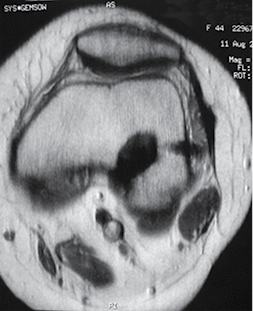

Un año posterior a la cirugía, acudió a consulta por presencia de dolor lateral a nivel de inserción distal de banda iliotibial en rodilla izquierda; se le indicó continuar con terapia física. Seis meses después acudió nuevamente con persistencia del dolor y de mayor intensidad, acompañado de contractura de banda iliotibial y dolor al flexionar con disminución en arcos de movimiento y presencia de protrusión de un pin en el Área Subcutánea del cóndilo femoral lateral de rodilla, con adecuada estabilidad ligamentaria. Se realizó resonancia magnética de rodilla, donde se observó fractura y migración del pin proximal hacia la región lateral de la rodilla sobre el trayecto de la banda iliotibial y presencia de inflamación (Figuras 1 y 2).

Figura 2: Corte axial de resonancia magnética en secuencia T1 donde se observa migración lateral del pin bioabsorbible.